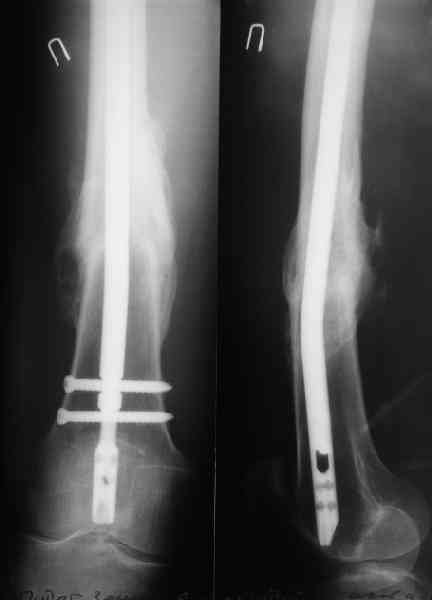

А на DFN свет клином не сошелся, мы используем отечественные штифты (MetaDiaFix, "ЦИТО"), которые можно вводить и ретроградно (4 винта), кроме того, в качестве ретроградного бедренного замечательно подходит большеберцовый гвоздь диаметром 12 мм.

В приложении как раз видна эволюция использововшихся у нас большеберцовых гвоздей. Первый - дизайн как у UTN, второй - разнесены 45 градусные отверстия (зачем их вообще изначально так нелепо на одном уровне сделалм???), третий - убрано сиавшее лишним статическое отверстие, Herzog's bend перемещен более проксимально.

Забавненько смотрится... "век живи, век учись", как говорится. А чья мысль использовать блокируемые штифты для б/берцовой кости при переломах бедра? Такое встречалось где-то в литературе или это ваше ноу-хау?

> А чья мысль использовать блокируемые штифты для б/берцовой кости

> при переломах бедра? Такое встречалось где-то в литературе или это

И в литературе есть:

=========================================

Rodgers WB, Kennedy JG, Coran DL, Goodman LJ, Lhowe DW. Retrograde intramedullary nailing of the femur using a tibial nail--the adjunctive use of an existing implant: a case report. Bull Hosp Jt Dis. 1996;55(2):78-80.

Эту ссылку нашли, есссно, после того, как уже стали делать ;-)

Насколько я помню, мы использовали этот вариант после знакомства с гвоздями SIGN, которые вообще одинаковые для бедра и голени, и дизайн у них большеберцовый.